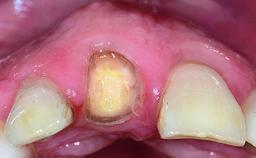

In 2008, a healthy 15-year-old female, non-smoking patient presented at our clinic with a major esthetic problem of tooth 21. Her dental history revealed that the tooth had been avulsed by trauma years before. As a result, the replanted and temporarily splinted tooth had ankylosed and was in severe apical malposition. The ankylosed tooth exhibited a significant gingival recession that disturbed the patient greatly. Due to the patient’s low age and with her skeletal growth not completed, periodic follow-up visits were scheduled to monitor the situation until the patient was old enough for implant therapy.

Soft Tissue Anatomy Intact Defective

Bone Volume Horizontally and vertically sufficient Horizontally deficient Deficient vertically or deficient vertically AND horizontally

Soft Tissue Contour and Volume Significantly deficient